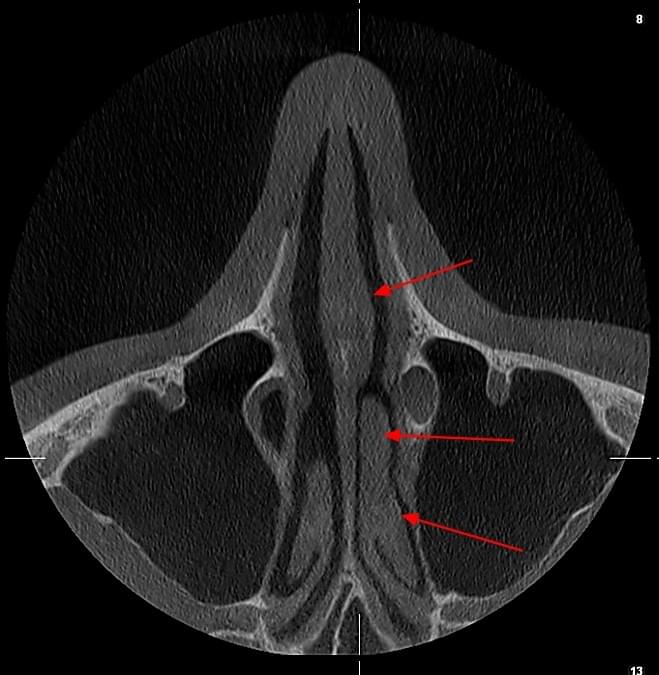

КПКТ (конусно-променева комп’ютерна томографія) — це 3D-знімок високої роздільної здатності. На відміну від звичайного рентгену, КТ показує:

У MyRayLab використовують сучасний апарат Planmeca 3D — доза опромінення всього 12 мкЗв (в 10–20 разів нижче, ніж у звичайних КТ), сканування 10 секунд, HD-якість.

КТ дозволяє провести віртуальну операцію: встановити імплант у програмі, виключивши будь-які ризики травмування пацієнта.